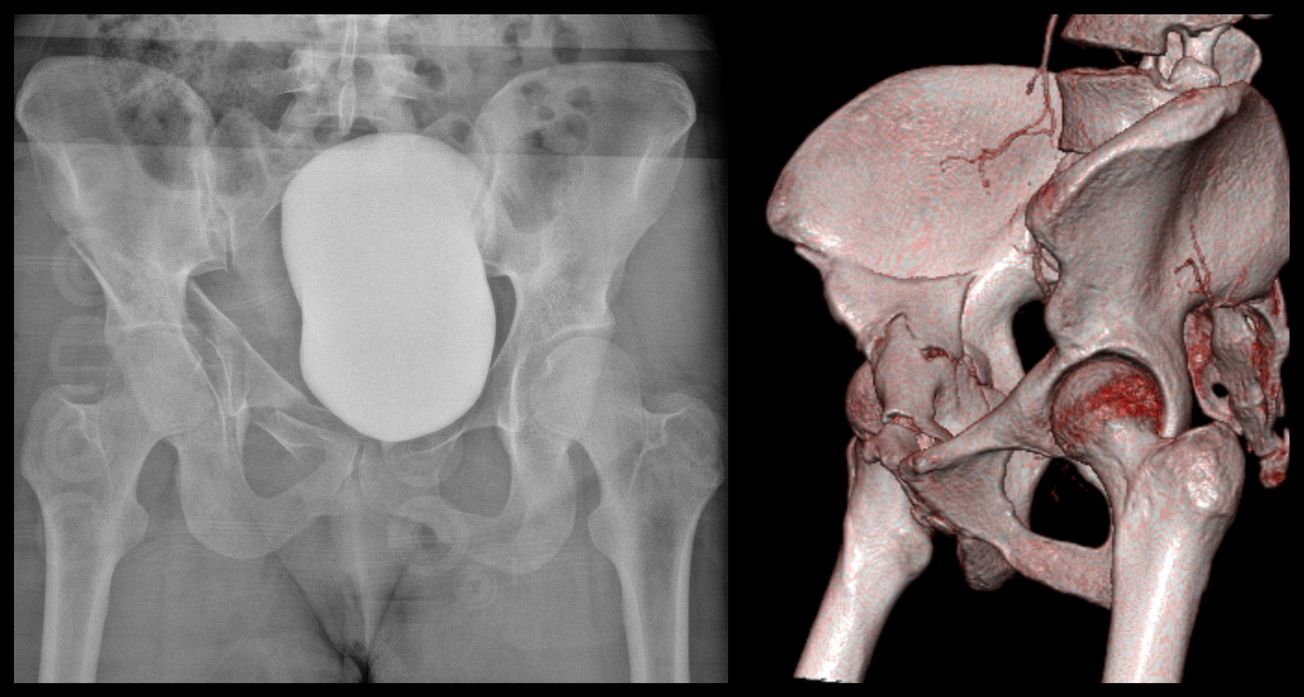

Anterior Column Acetabulum ORIF

David Rothberg

April 16, 2022